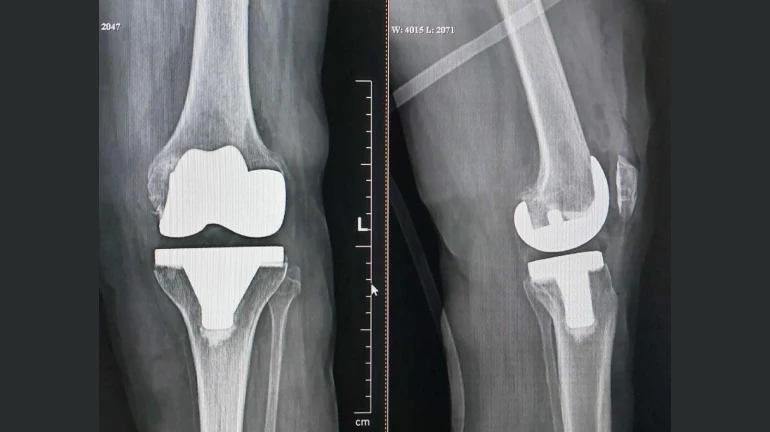

Dr. Dhananjay Parab, Knee Replacement Surgeon, Zynova Shalby Hospital, Mumbai Said, ‘‘The woman could not walk due to severe pain and deformity in both her knees. In the medical report, it has been seen that the knee of the left leg of this woman has been damaged. In such a situation knee replacement surgery was the only option. In this regard, the surgery was performed with the permission of the family. The woman was able to stand on her feet again just hours after the surgery. Two days after the surgery, the woman was discharged.’’

‘‘The woman was born with club foot, however it was not treated well, leading to a deformed foot. In such a situation, the problem of arthritis arises in the future. She had knee problems comparatively early due to club foot. Apart from this, the woman was suffering from diabetes and high blood pressure. Under such conditions, doing knee replacement surgery was a challenge. Yet, In this scenario doctors performed a successful knee replacement surgery," Dr. Parab added.